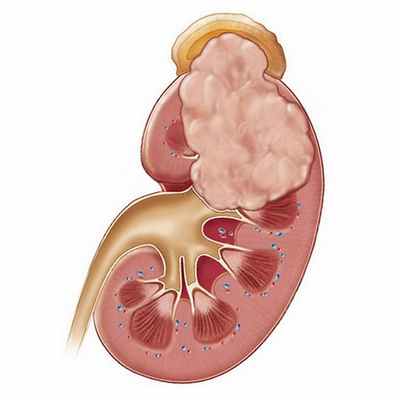

Метастазы в надпочечниках

Метастазы надпочечников — это вторичные очаги, которые возникают в результате распространения раковых клеток из злокачественных опухолей, находящихся в других органах, как правило, с током крови (гематогенно). Надпочечники — достаточно частое место локализации метастатических очагов, за счет богатого кровоснабжения. Вторичные опухоли встречаются в этих органах намного чаще, чем первичные, и зачастую их сложно диагностировать бессимптомного течения.

Надпочечники представляют собой небольшие железы, которые находятся у верхних полюсов почек. Они вырабатывают многие гормоны: адреналин, норадреналин, глюкокортикоиды, минералкортикоиды, андрогены, альдостерон и др.

По результатам патологоанатомических вскрытий, вторичные очаги в надпочечниках обнаруживаются у 27% пациентов с эпителиальными злокачественными опухолями.